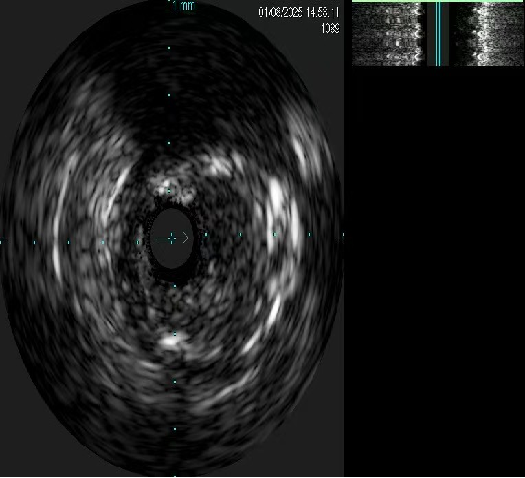

右冠血管内超声影像(IVUS)

对侧造影证实GW3位于远端真腔,跟进微导管,撤出GW3送入GW1,先后送入balloon 1(1.5x1.5mmEmerge)、Ballon 2(2.0x15mmGusta)、Ballon3 (2.0x15mm 心迅)、Ballon 4(2.5x15mm cutting)、Ballon5(2.5x15mm NC Sprinter)、Ballon 6(3.0x15mm NC Sprinter)至RCA病变处预处理后,送入IVUS查看病变性质、程度及血管直径。

送入IVUS导管查看支架开放良好、贴壁良好,未见夹层、血栓等 并发症。